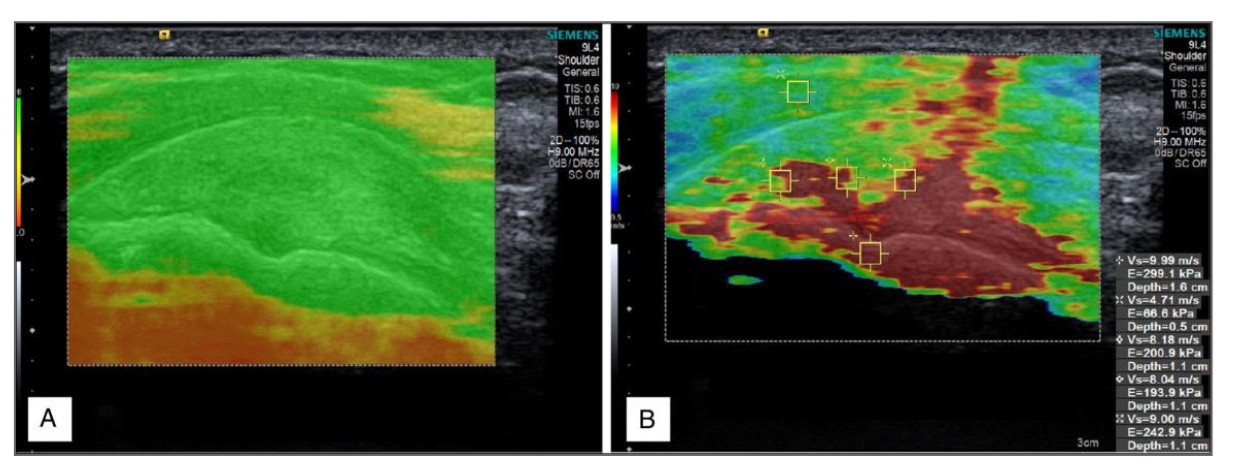

Figure 1. Standard B-mode ultrasound (A) compared with shear-wave elastography of the supraspinatus tendon (B).

Shear-wave elastography is an advanced ultrasound technique that quantifies tissue stiffness in real time. It measures the speed at which ultrasound generated shear waves travel through tissue — with stiffer tissues transmitting waves faster.

- Objective, numerical measurements of stiffness (kPa or m/s)

- Colour-coded maps of tendon properties